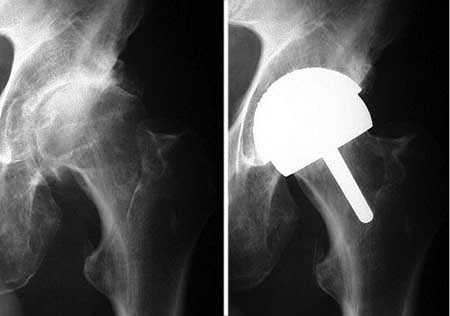

Оставить как есть ненадо, т. к. отломок перевёрнут на 180 градусов, а чтобы делать остеосинтез время упущено, большая вероятность что закончится асептическим некрозом, в приложенном файле подходящий эндопротез для него.

Имя     : resurf.jpg